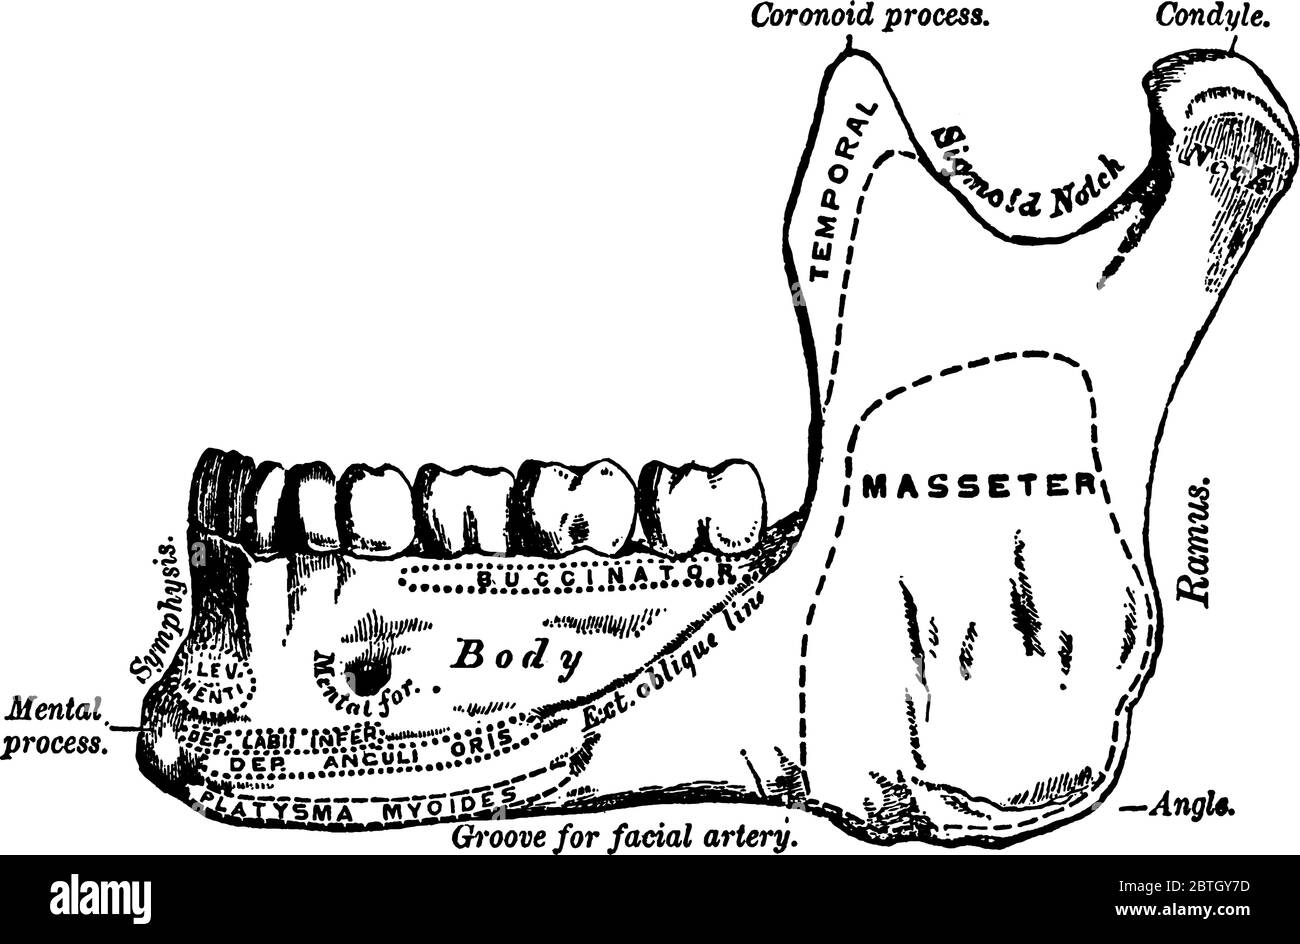

L'os le plus grand et le plus fort du visage et sert à la réception des dents inférieures, avec ses parties étiquetées, vintage dessin de ligne ou gravure Illustration de Vecteurhttps://www.alamyimages.fr/image-license-details/?v=1https://www.alamyimages.fr/l-os-le-plus-grand-et-le-plus-fort-du-visage-et-sert-a-la-reception-des-dents-inferieures-avec-ses-parties-etiquetees-vintage-dessin-de-ligne-ou-gravure-image359331713.html

L'os le plus grand et le plus fort du visage et sert à la réception des dents inférieures, avec ses parties étiquetées, vintage dessin de ligne ou gravure Illustration de Vecteurhttps://www.alamyimages.fr/image-license-details/?v=1https://www.alamyimages.fr/l-os-le-plus-grand-et-le-plus-fort-du-visage-et-sert-a-la-reception-des-dents-inferieures-avec-ses-parties-etiquetees-vintage-dessin-de-ligne-ou-gravure-image359331713.htmlRF2BTGY7D–L'os le plus grand et le plus fort du visage et sert à la réception des dents inférieures, avec ses parties étiquetées, vintage dessin de ligne ou gravure

Cette illustration représente Les Muscles de la mâchoire inférieure, du dessin vintage ou de l'illustration de gravure. Illustration de Vecteurhttps://www.alamyimages.fr/image-license-details/?v=1https://www.alamyimages.fr/cette-illustration-represente-les-muscles-de-la-machoire-inferieure-du-dessin-vintage-ou-de-l-illustration-de-gravure-image348653222.html

Cette illustration représente Les Muscles de la mâchoire inférieure, du dessin vintage ou de l'illustration de gravure. Illustration de Vecteurhttps://www.alamyimages.fr/image-license-details/?v=1https://www.alamyimages.fr/cette-illustration-represente-les-muscles-de-la-machoire-inferieure-du-dessin-vintage-ou-de-l-illustration-de-gravure-image348653222.htmlRF2B76EMP–Cette illustration représente Les Muscles de la mâchoire inférieure, du dessin vintage ou de l'illustration de gravure.